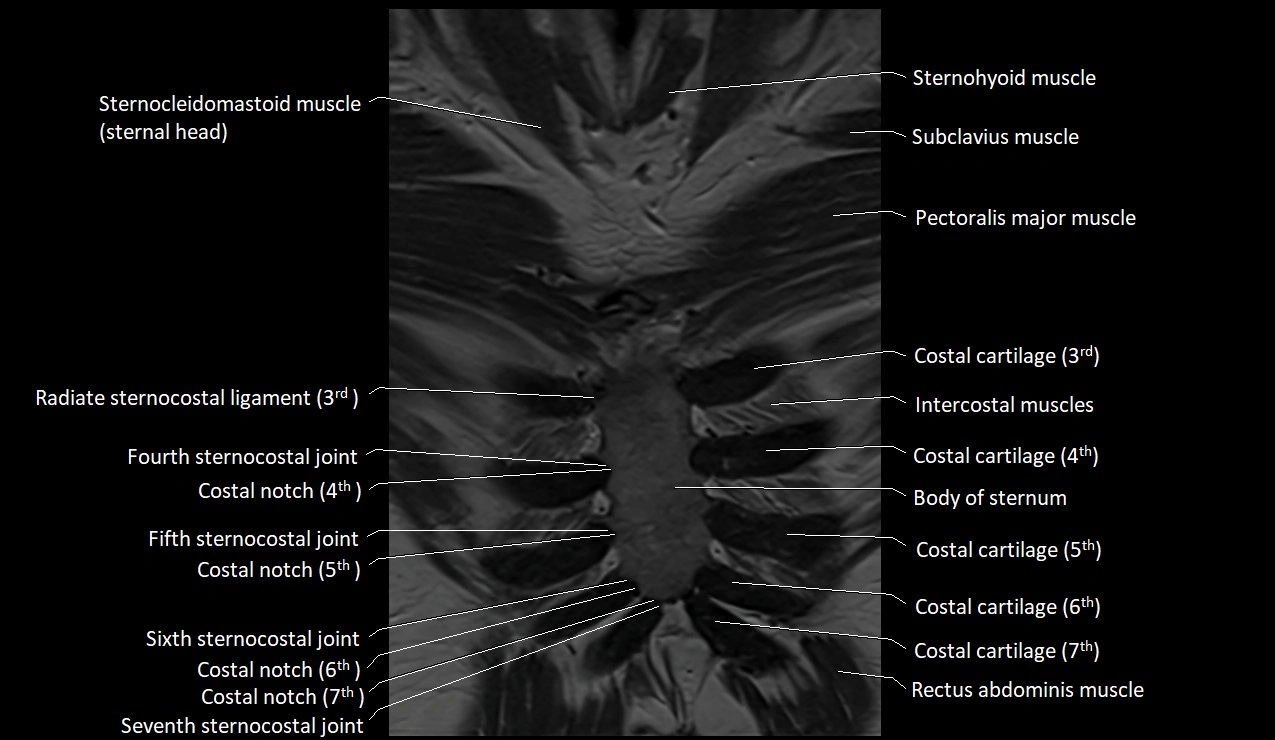

MRI images

image